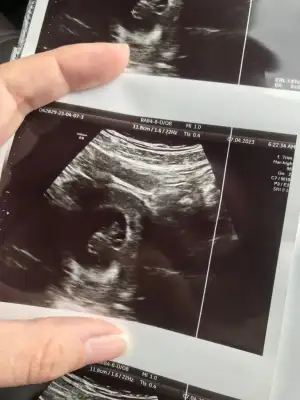

Uzun zamandır okuyorum ama ilk kez yazıyorum :) ne kadar okusamda ramzi ve nub teoirilerini anlayamadım bir türlü. Tüp bebek tedavisi sonucu hamile kaldım , sırasıyla 6 hafta,8 hafta ve son olarak 12+2 haftalık görüntülerimizi ekliyorum benim içinde cinsiyet tahmini yapar mısınız lütfen :)

• IMG_3129.webp

IMG_3129.webp

38,9 KB · Görüntüleme: 70